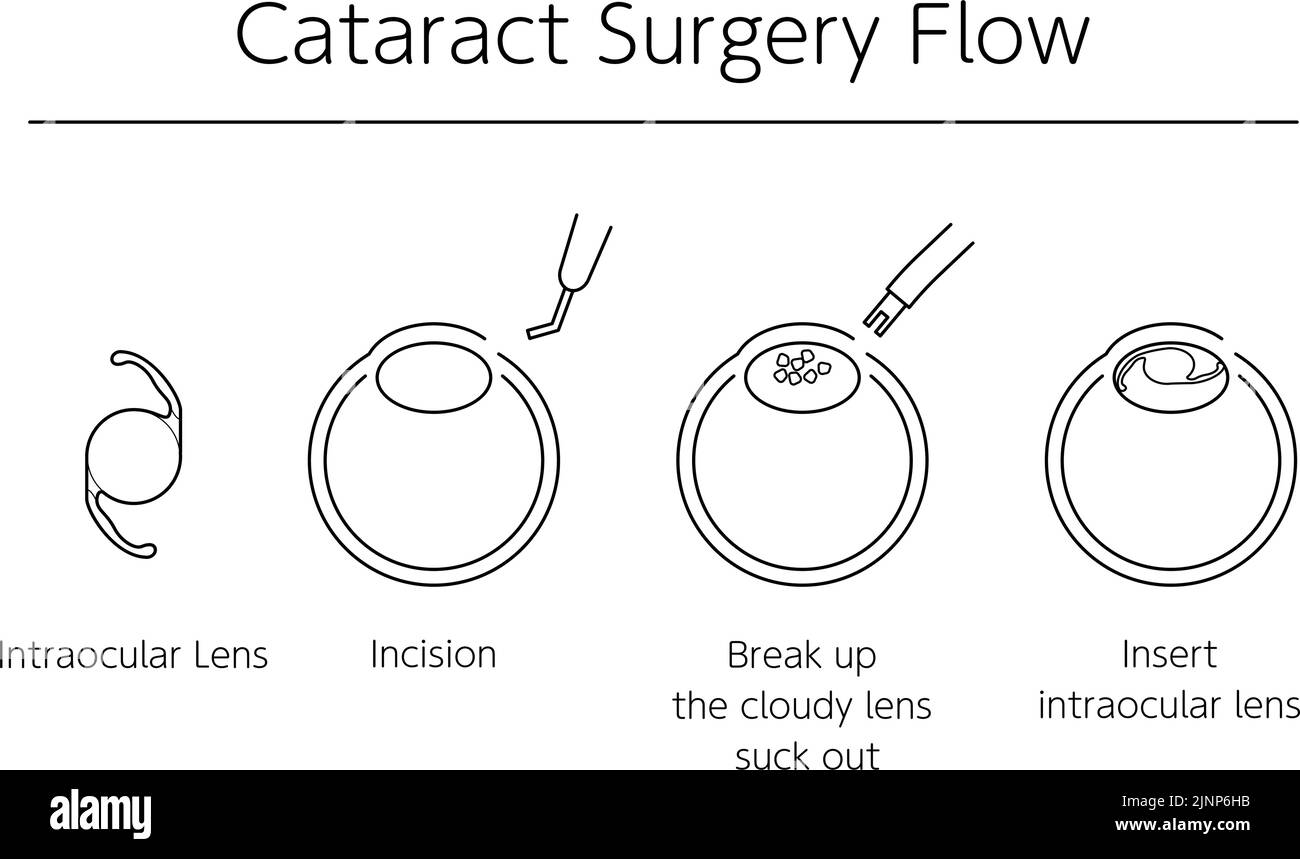

Flow of cataract surgery, illustrated illustration (line drawing) Stock Vectorhttps://www.alamy.com/image-license-details/?v=1https://www.alamy.com/flow-of-cataract-surgery-illustrated-illustration-line-drawing-image478075847.html

Flow of cataract surgery, illustrated illustration (line drawing) Stock Vectorhttps://www.alamy.com/image-license-details/?v=1https://www.alamy.com/flow-of-cataract-surgery-illustrated-illustration-line-drawing-image478075847.htmlRF2JNP6HB–Flow of cataract surgery, illustrated illustration (line drawing)

Flow of cataract surgery, illustrated illustration (line drawing) - Translation: flow of cataract surgery, intraocular lens, making incision, sucking Stock Vectorhttps://www.alamy.com/image-license-details/?v=1https://www.alamy.com/flow-of-cataract-surgery-illustrated-illustration-line-drawing-translation-flow-of-cataract-surgery-intraocular-lens-making-incision-sucking-image478076717.html

Flow of cataract surgery, illustrated illustration (line drawing) - Translation: flow of cataract surgery, intraocular lens, making incision, sucking Stock Vectorhttps://www.alamy.com/image-license-details/?v=1https://www.alamy.com/flow-of-cataract-surgery-illustrated-illustration-line-drawing-translation-flow-of-cataract-surgery-intraocular-lens-making-incision-sucking-image478076717.htmlRF2JNP7MD–Flow of cataract surgery, illustrated illustration (line drawing) - Translation: flow of cataract surgery, intraocular lens, making incision, sucking